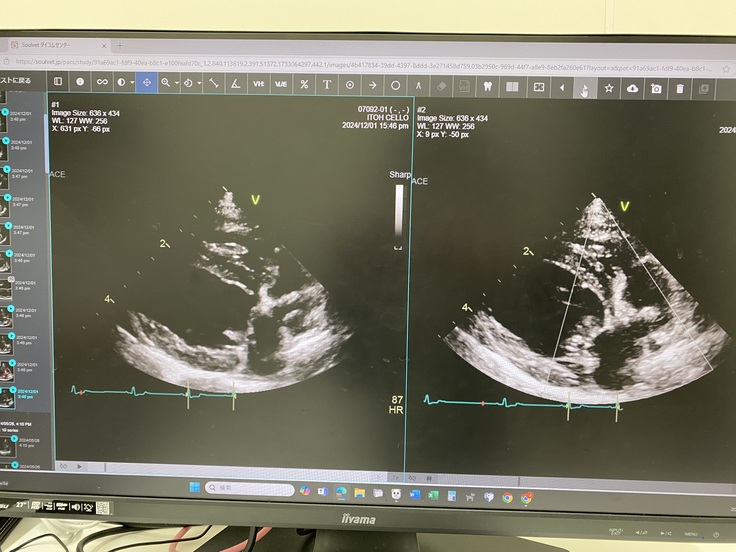

12月1日に2ヶ月遅れの1年検診に

行ってきました🚗 ³₃

今回も結果は良好でした😆✨️

血液の逆流がなく、弁の形もとっても綺麗だから再発する可能性はかなり低いと仰ってました😊✨️

そして、血液検査もGood✨️💮💯

「11歳でこの結果は素晴らしい✨️」とお褒めの言葉をいただきました😊

経過が良かったので、次の検診は一年後になりました☺️✨️